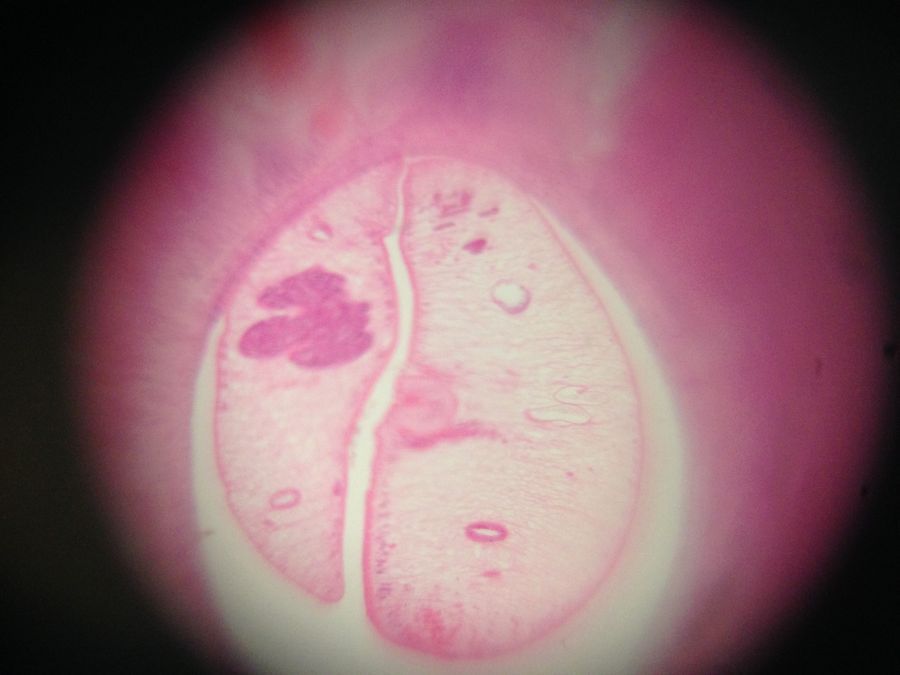

Foldscope number: 0001CFC71A56 , liver fluke: the two small circles on either side (that look like eyes) are the two intestinal branches (diagnostic for Chlonorchis sinensis ). The fluke is in a bile duct, this may be two flukes or one that is folded in two. The bile duct around it is enlarged and with inflammatory cells.

Foldscope number: 0001 9BEA 448C, malaria brain: haemorrhaging and pigment clearly visible in pinkish area in the centre